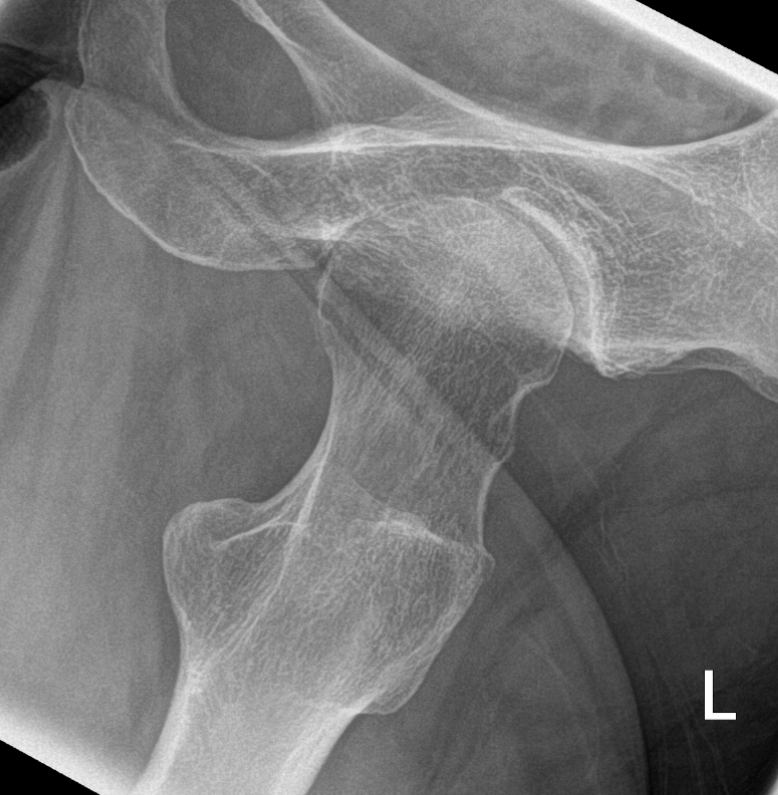

3. Osteoarthritis of hip seen on Dunne view